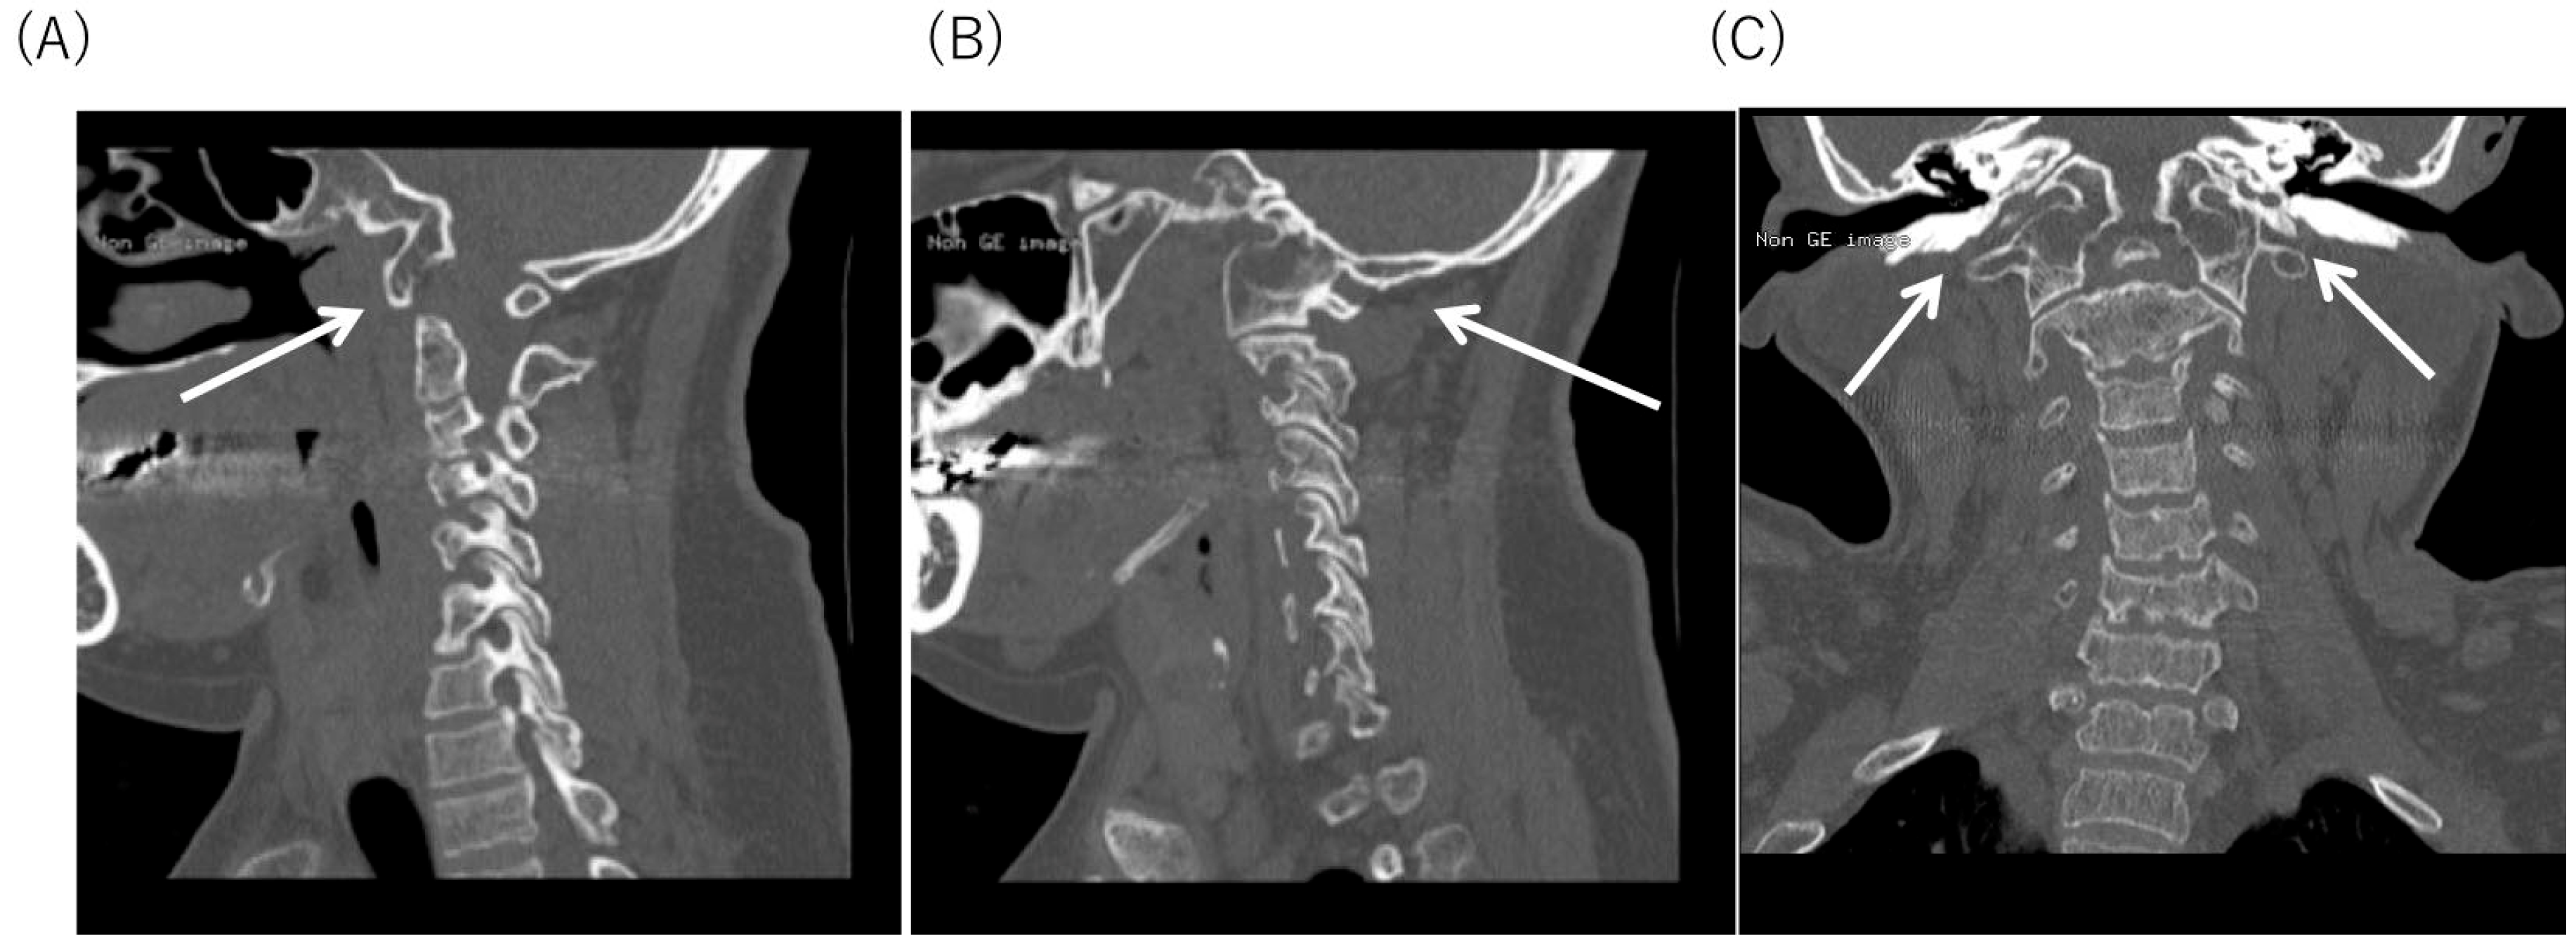

2.4. Radiological Findings